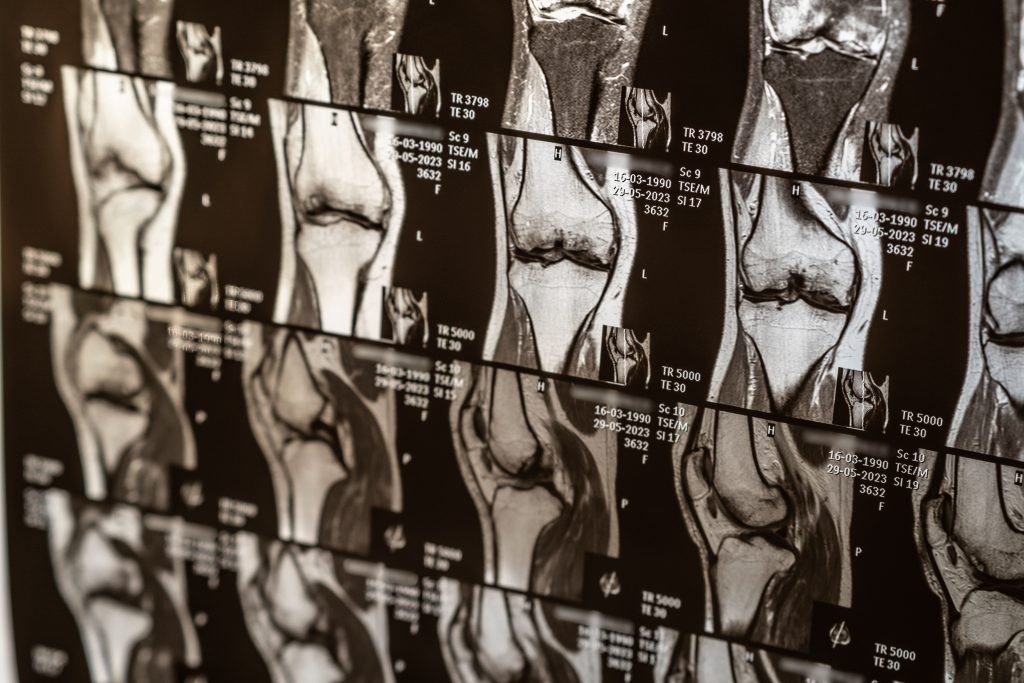

Protocolos de exame

Os protocolos de RM para lesões esportivas variam de acordo com a área a ser examinada, mas normalmente incluem sequências T1, T2, STIR ou PD Fat Sat, que permitem identificar tanto a anatomia normal quanto as alterações patológicas.